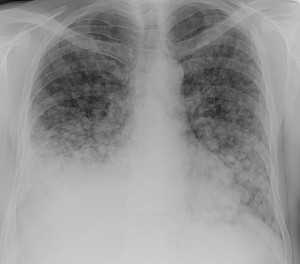

Лимфогенные метастазы на рентгене и КТ выглядят как множественные мелкие очаги с диссеминированным распространением, локализованные в междольковых перегородках, в плевральных листках. Вокруг можно видеть характерную картину ракового лимфангиита. Кроме того, практически всегда выявляются патологически измененные и увеличенные лимфатические узлы средостения. Лимфогенное метастазирование необходимо дифференцировать с милиарным туберкулезом, саркоидозом. Иногда это требует привлечения Второго мнения.

КТ: метастазы в легких при раке молочной железы. На изображении справа красной звездочкой отмечен опухолевый узел в молочной железе, красными стрелками - область прорастания опухоли в грудную стенку. Синими звездочками отмечен карциноматозный плеврит — скопление жидкости в плевральной полости. Слева стрелкой отмечен вторичный узел.

Лимфогенные метастазы проявляются увеличением лимфатических узлов средостения в сочетании с мелкоочаговой диссеминацией с очагами до 2-3 мм в диаметре вблизи плевры и в междольковых перегородках, а также по ходу бронхов и сосудистых пучков.